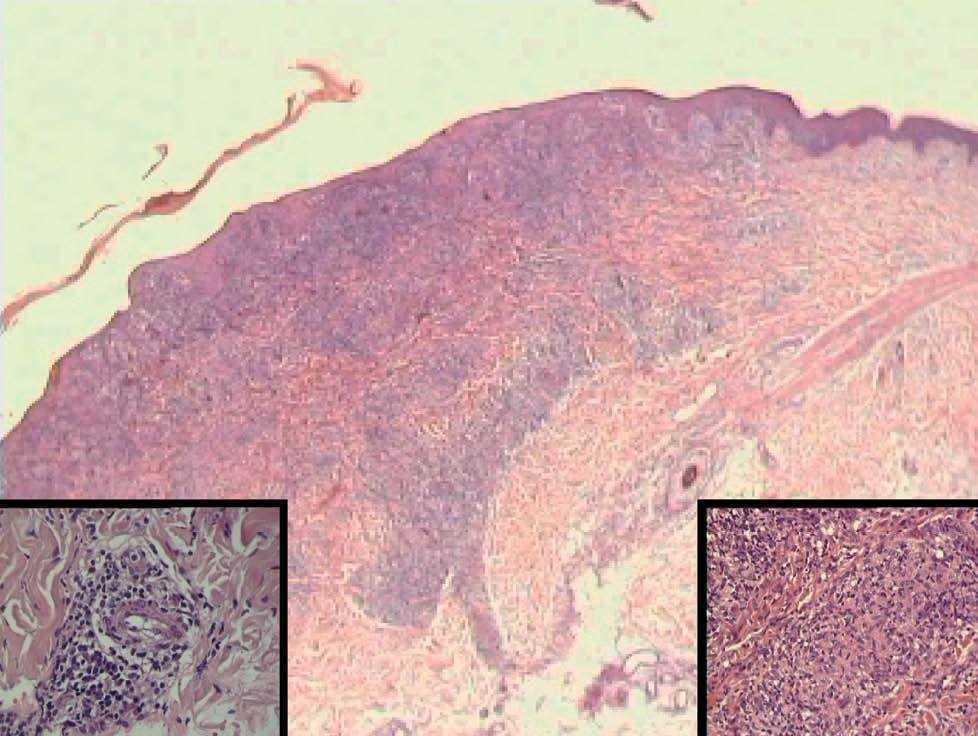

La histología mostraba leve paraqueratosis, con focos de neutrófilos formando costra, abundantes queratinocitos necróticos y un intenso infiltrado inflamatorio, que afectaba a las dermis superficial y profunda. El infiltrado era linfohistiocitario, con acentuación perivascular y presencia de células plasmáticas, produciendo cambios vacuolares basales y escasos focos de espongiosis (fig. 3). Se identificaba tumefacción endotelial en la dermis superficial y ocasionales fenómenos vasculíticos.

Fig. 3.--En la visión panorámica, a pequeño aumento se aprecia un infiltrado inflamatorio en la interfase y en la dermis profunda (Hematoxilina-eosina, x10). Detalle a la izquierda de un endotelio tumefacto con un infiltrado inflamatorio perivascular linfoplasmocitario (H-E, x40). A la derecha se aprecia una lesión granulomatosa en la dermis (H-E, x40).